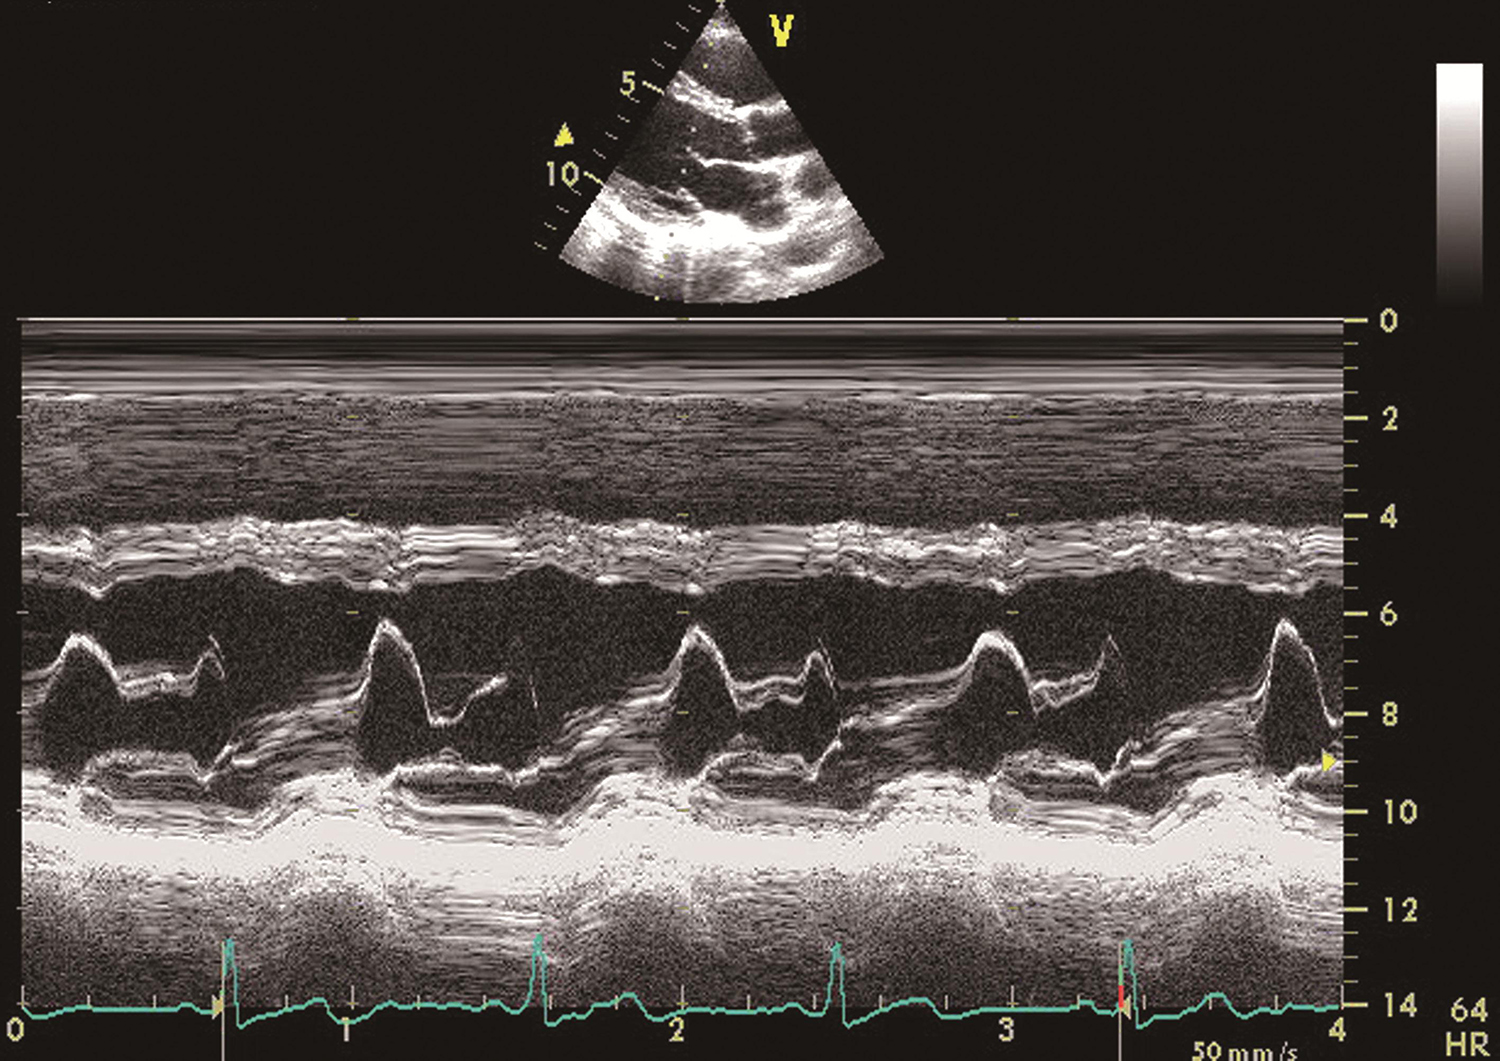

以纵轴为深度,横轴为时间。将各层组织界面在声束内位置移动随时间的变化以位移-时间动态曲线显示(图1-1-3-4),具有非常高的时间分辨力。

图1-1-3-4 M型成像

显示心动周期内室间隔、二尖瓣、左心室后壁的运动。